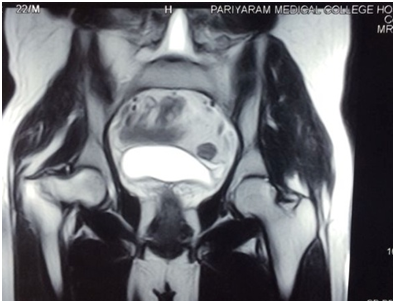

Operative procedure was done on a standard fracture table under image intensifier control. Through anterolateral approach (Watson-Jones), the proximal femur was approached. Firstly a cannulated cancellous derotation screw was inserted through the neck into superior aspect of the neck. A 135 -degree DHS side plate was inserted and site of osteotomy was marked at the level of angle of plate by drilling a transverse K wire at that level under C-arm. Oblique osteotomy was done firstly proximally directing towards the lesser trochanter and then osteotomy was completed by oscillating bone saw. Predetermined size of wedge was removed.The removed wedge was morcellated and used for bone graft around the osteotomy site and nonunion field. The pointed part of the proximal part of the distal part is cut so that a triangular wedge is achieved. This is further cut in to two parts. The remaining part is docked to the proximal segment. The gap is filled with cut parts.The barrel plate was fixed with cortical screws and compression screw was inserted in the hip lag screw to compress the fracture site as much as feasible. Wound was closed in layers after leaving suction.The operation period was 150 min and the amount of blood loss was about 400 ml. Post operative radiograph was taken (Figure 3).

Figure 3 Immediate Post -operative radiograph.